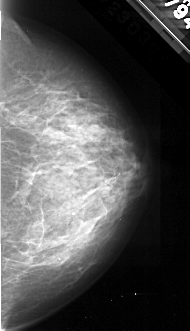

A_1097_1.RIGHT_MLO

RIGHT_MLO LINES 5161 PIXELS_PER_LINE 2326 BITS_PER_PIXEL 16 RESOLUTION 42 NON_OVERLAY